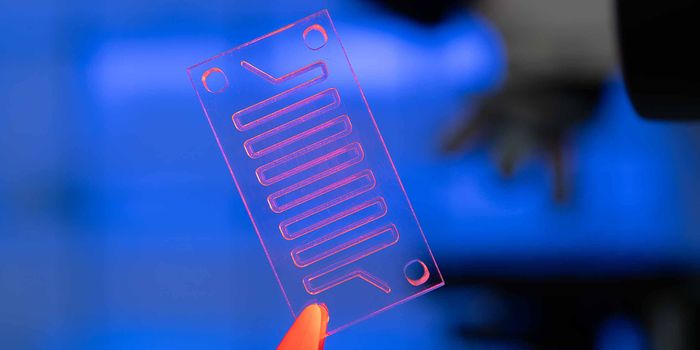

DEC 08, 2021Clinical & Molecular DXBy Julianne Davis - Technical Writer and Support Scientist at Biotium The Rise of the Lab-on-a-Chip With the advent of m ...

NOV 02, 2016Chemistry & PhysicsDiagnosing Sepsis Earlier to Save Lives Using Microfluidics